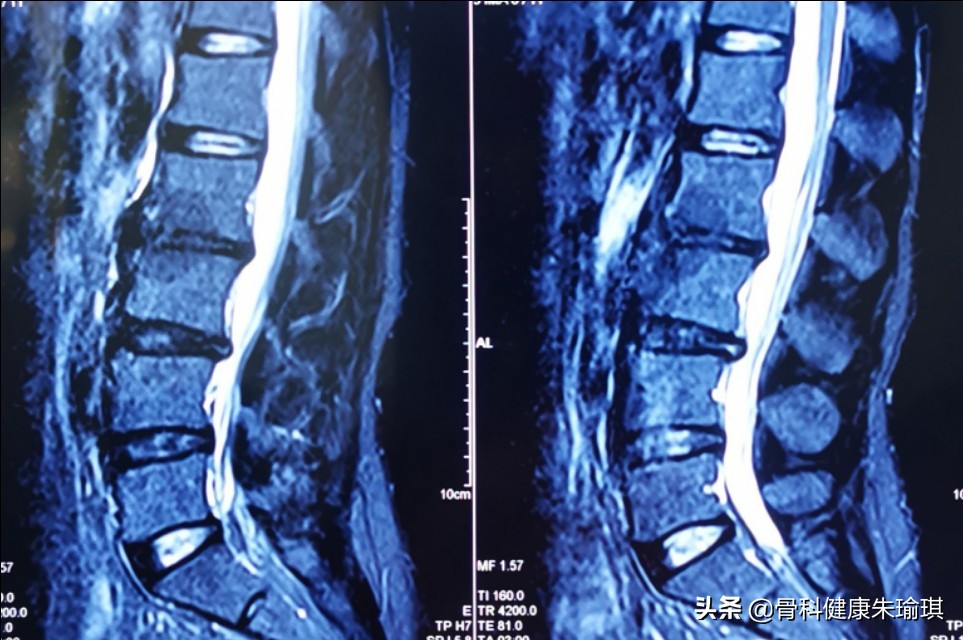

人们对腰椎间盘突出症影像学转归方面的认识也不断深入。其最早可追溯到1984年, Guinto首次对腰椎间盘突出症患者的保守治疗结果进行了CT随访,观察到突出的椎间盘组织可以缩小或者消失,并称之为”自发性消退( spontaneous regression)”,这个发现开启了腰椎间盘突出后重吸收研究的先河。国内姜宏1998年率先在《中华骨科杂志》发表了《腰椎间盘突出后的自然吸收及其临床意义》一文,介绍了国外对突出椎间盘重吸收现象的影像学观察及其机理研究的新进展。2016年4月份Hong等在《新英格兰医学杂志》发表了一篇关于1名29岁女性椎间盘突出后重吸收的病例报道,再次引起了国际医学界的广泛关注。随着对重吸收现象研究的不断深入,人们发现重吸收的机制主要包括炎症免疫等方面。但令人遗憾的是,人们在药物引发产生重吸收的机制,促进重吸收现象的产生方面的研究仍是空白。

近年来腰椎间盘突出症的治疗方法正在朝微创或无创技术方向发展。目前研究表明突出椎间盘重吸收现象有多种机制参与,其机制涵盖了生理病理、生物力学、遗传衰老和免疫等诸多医学基础领域,尽管现代医学手术技术发展迅猛,但是有一点不可否认:大多数腰椎间盘突出症可经非手术治疗缓解甚至治愈,这使我们对某些过早、过度甚至扩大指证进行手术的现象予以反思。